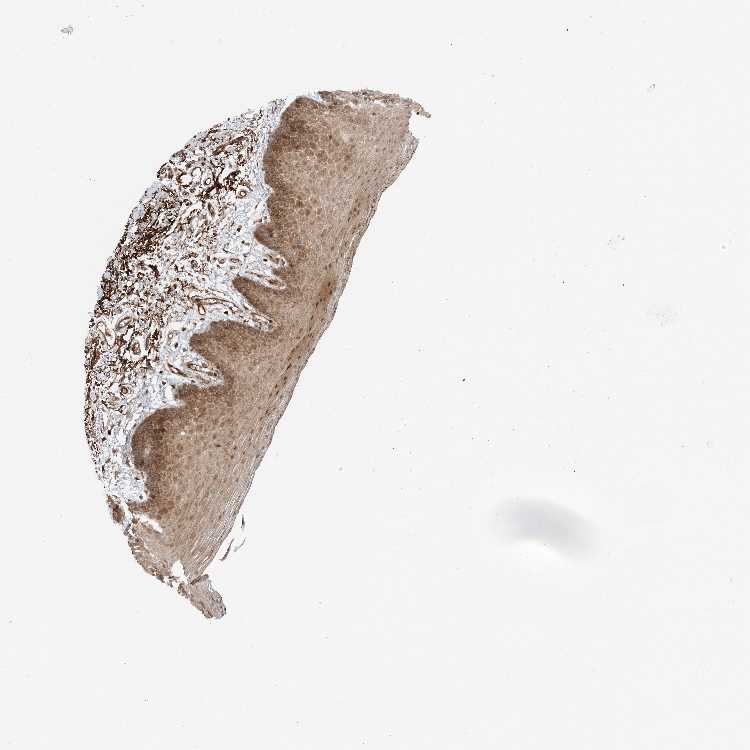

TISSUE PRIMARY DATA ORAL MUCOSA Show tissue menu

ORAL MUCOSA - Antibody stainingi

Antibody staining in the annotated cell types in the current human tissue is reported as not detected, low, medium, or high, based on conventional immunohistochemistry profiling in selected tissues. This score is based on the combination of the staining intensity and fraction of stained cells.

Each image is clickable and will lead to virtual microscopy that enables deeper exploration of all samples and also displays staining intensity scores, fraction scores and subcellular localization as well as patient and tissue information for each sample.

Antibody HPA037393

Squamous epithelial cells Medium